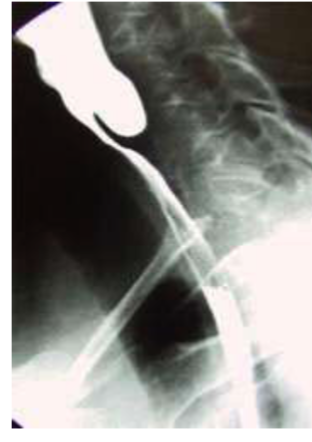

Zenkerโs Diverticulum

- Question: A 62- year- old male with dysphagia, halitosis and regurgitation of undigested food.

- Answer:

- A-What is the name of the test?

- Barium swallow

- B-What is the diagnosis?

- pharyngeal pouch or Zenkerโs Diverticulum

- C- Whatโs the treatment?

- Cricopharyngeal myotomy. (Botox) the issue of this is that we have to repeat the same thing after 4 months.

- Diverticulectomy (we can say surgical excision) more preferred due to less complications.

Pharyngeal Pouch or Zenkerโs Diverticulum

An 80-year-old male presented with a 2-year history of dysphagia and food regurgitation. - A 62-year-old male with dysphagia, halitosis, and regurgitation of undigested food.

- Diagnosis: Pharyngeal pouch or Zenkerโs diverticulum.

- Study: Barium swallow.

- Management: Cricopharyngeal myotomy, diverticulectomy.